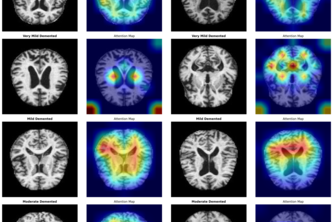

I created an explainable deep learning system that detects early Alzheimer’s disease (AD) from MRI scans with calibrated confidence, to help clinicians identify at-risk patients sooner.